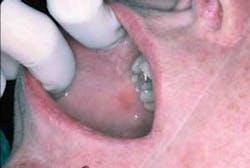

Your patient today is a 34 year-old female who has made an appointment to determine the etiology of an erythematous patch on her right buccal mucosa. She noticed this painless, nonulcerative red area approximately a year ago, but decided to wait until she established a dental office and could make an appointment.

As you evaluate the area, you notice that the erythematous lesion is adjacent to an amalgam restoration. The patient had the restoration placed about 14 months ago — before a job relocation.

After assessing the restoration and later replacing the amalgam with a non-metal restoration, the lesion subsided. It was determined that the cause was due to a sensitivity to the metal components in the restoration or a “contact lichenoid reaction” (see Figure 1).

In the case presented, the reddened area is in contact with the amalgam restoration. The tissue reaction may be around adjacent tissue or possibly at the gingival margin if the restoration extends into the gingival tissue.